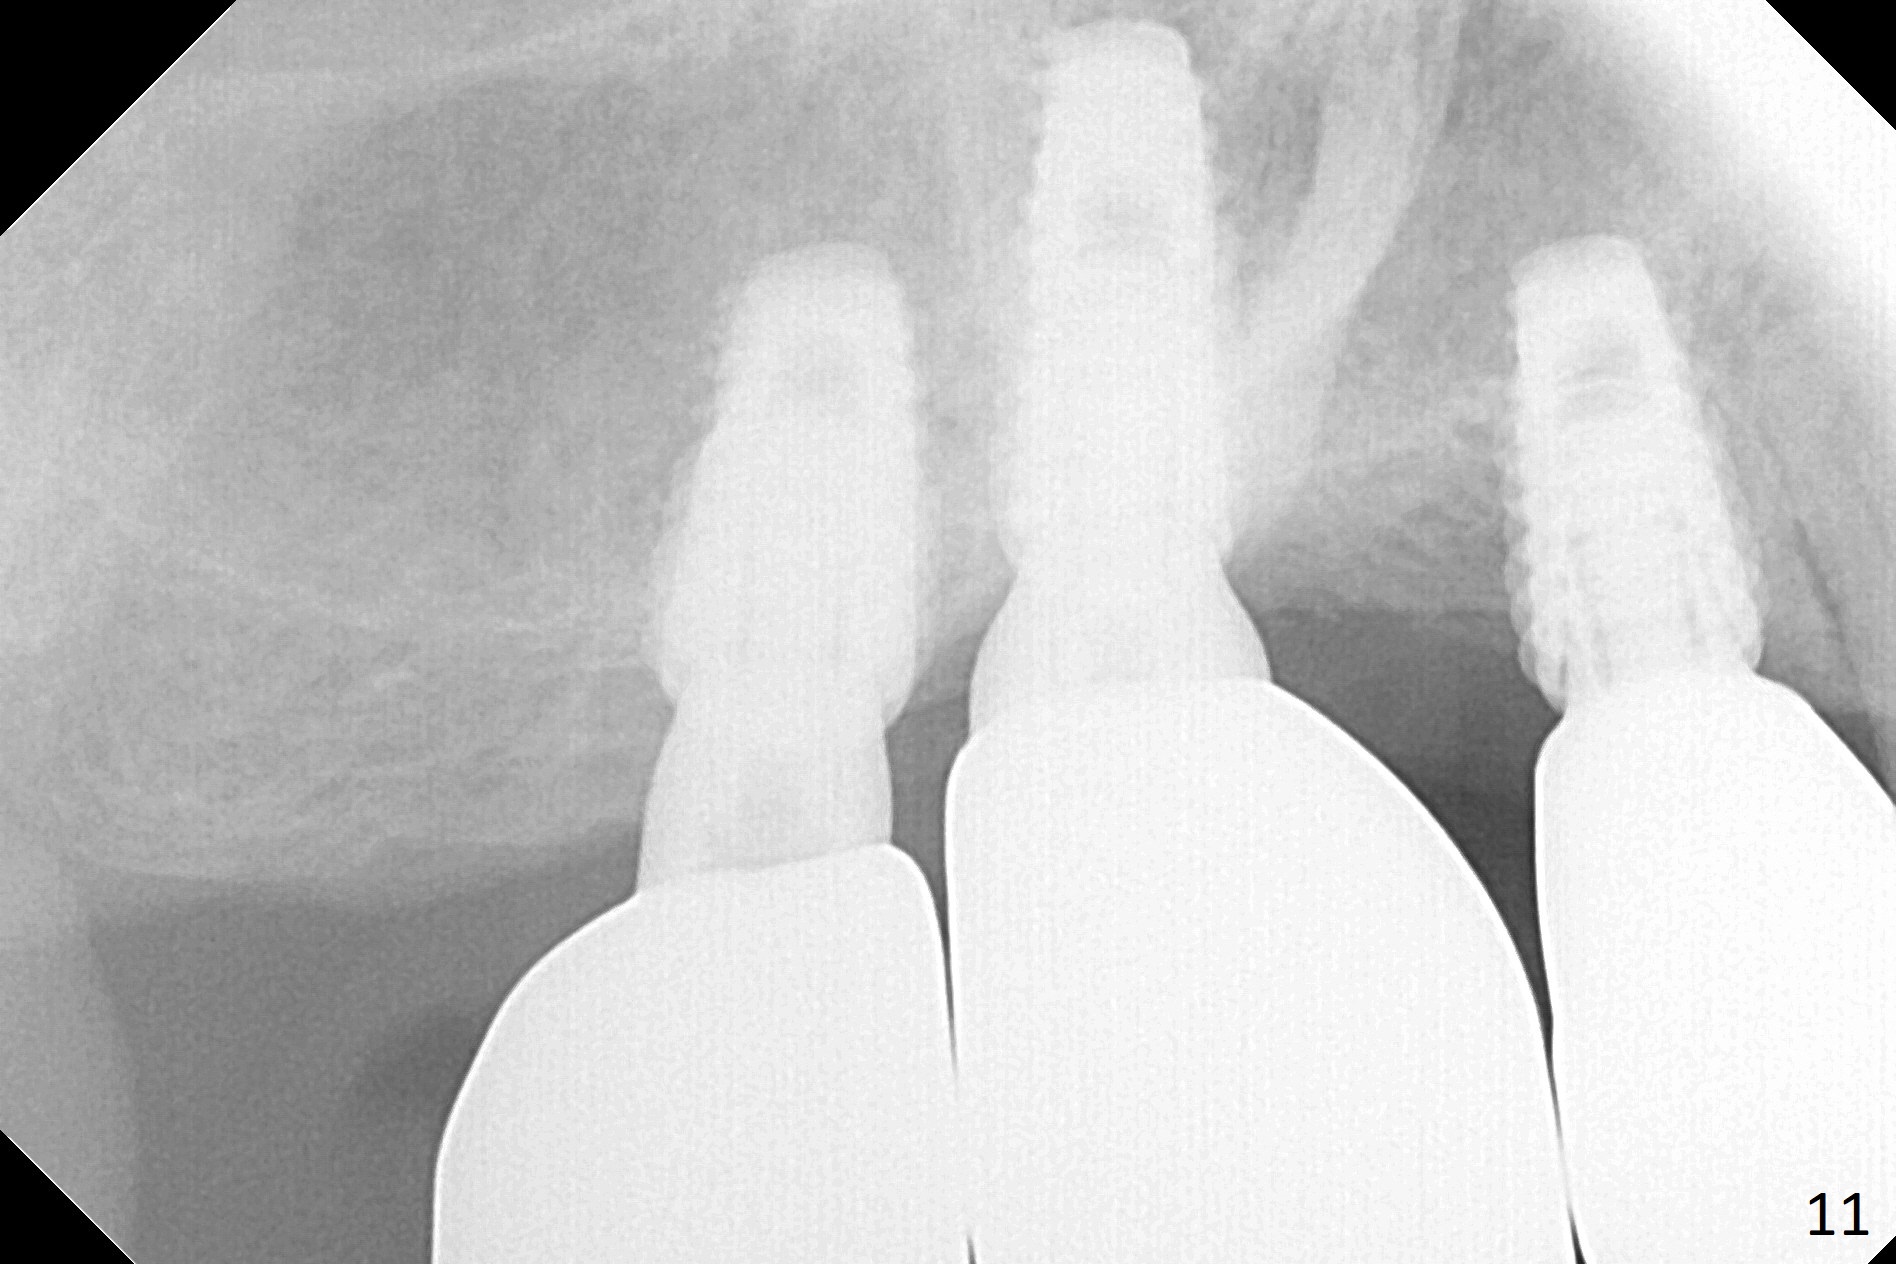

In fact, these implants seem to heal normally 2.5 months post (Fig.10). After change in abutments at #2 (from 5.5x7(4) to 4.5x5.5(5) mm) and #4 (from 5.5x7(2) to 4.5x5.5(1) mm) and torquing, impression is taken. The implant at #3 appears to be associated with the septal bone (Fig.10 *). There is no apparent bone loss 1 years 4 months post cementation (Fig.11). The patient will return for 14,15 implants.